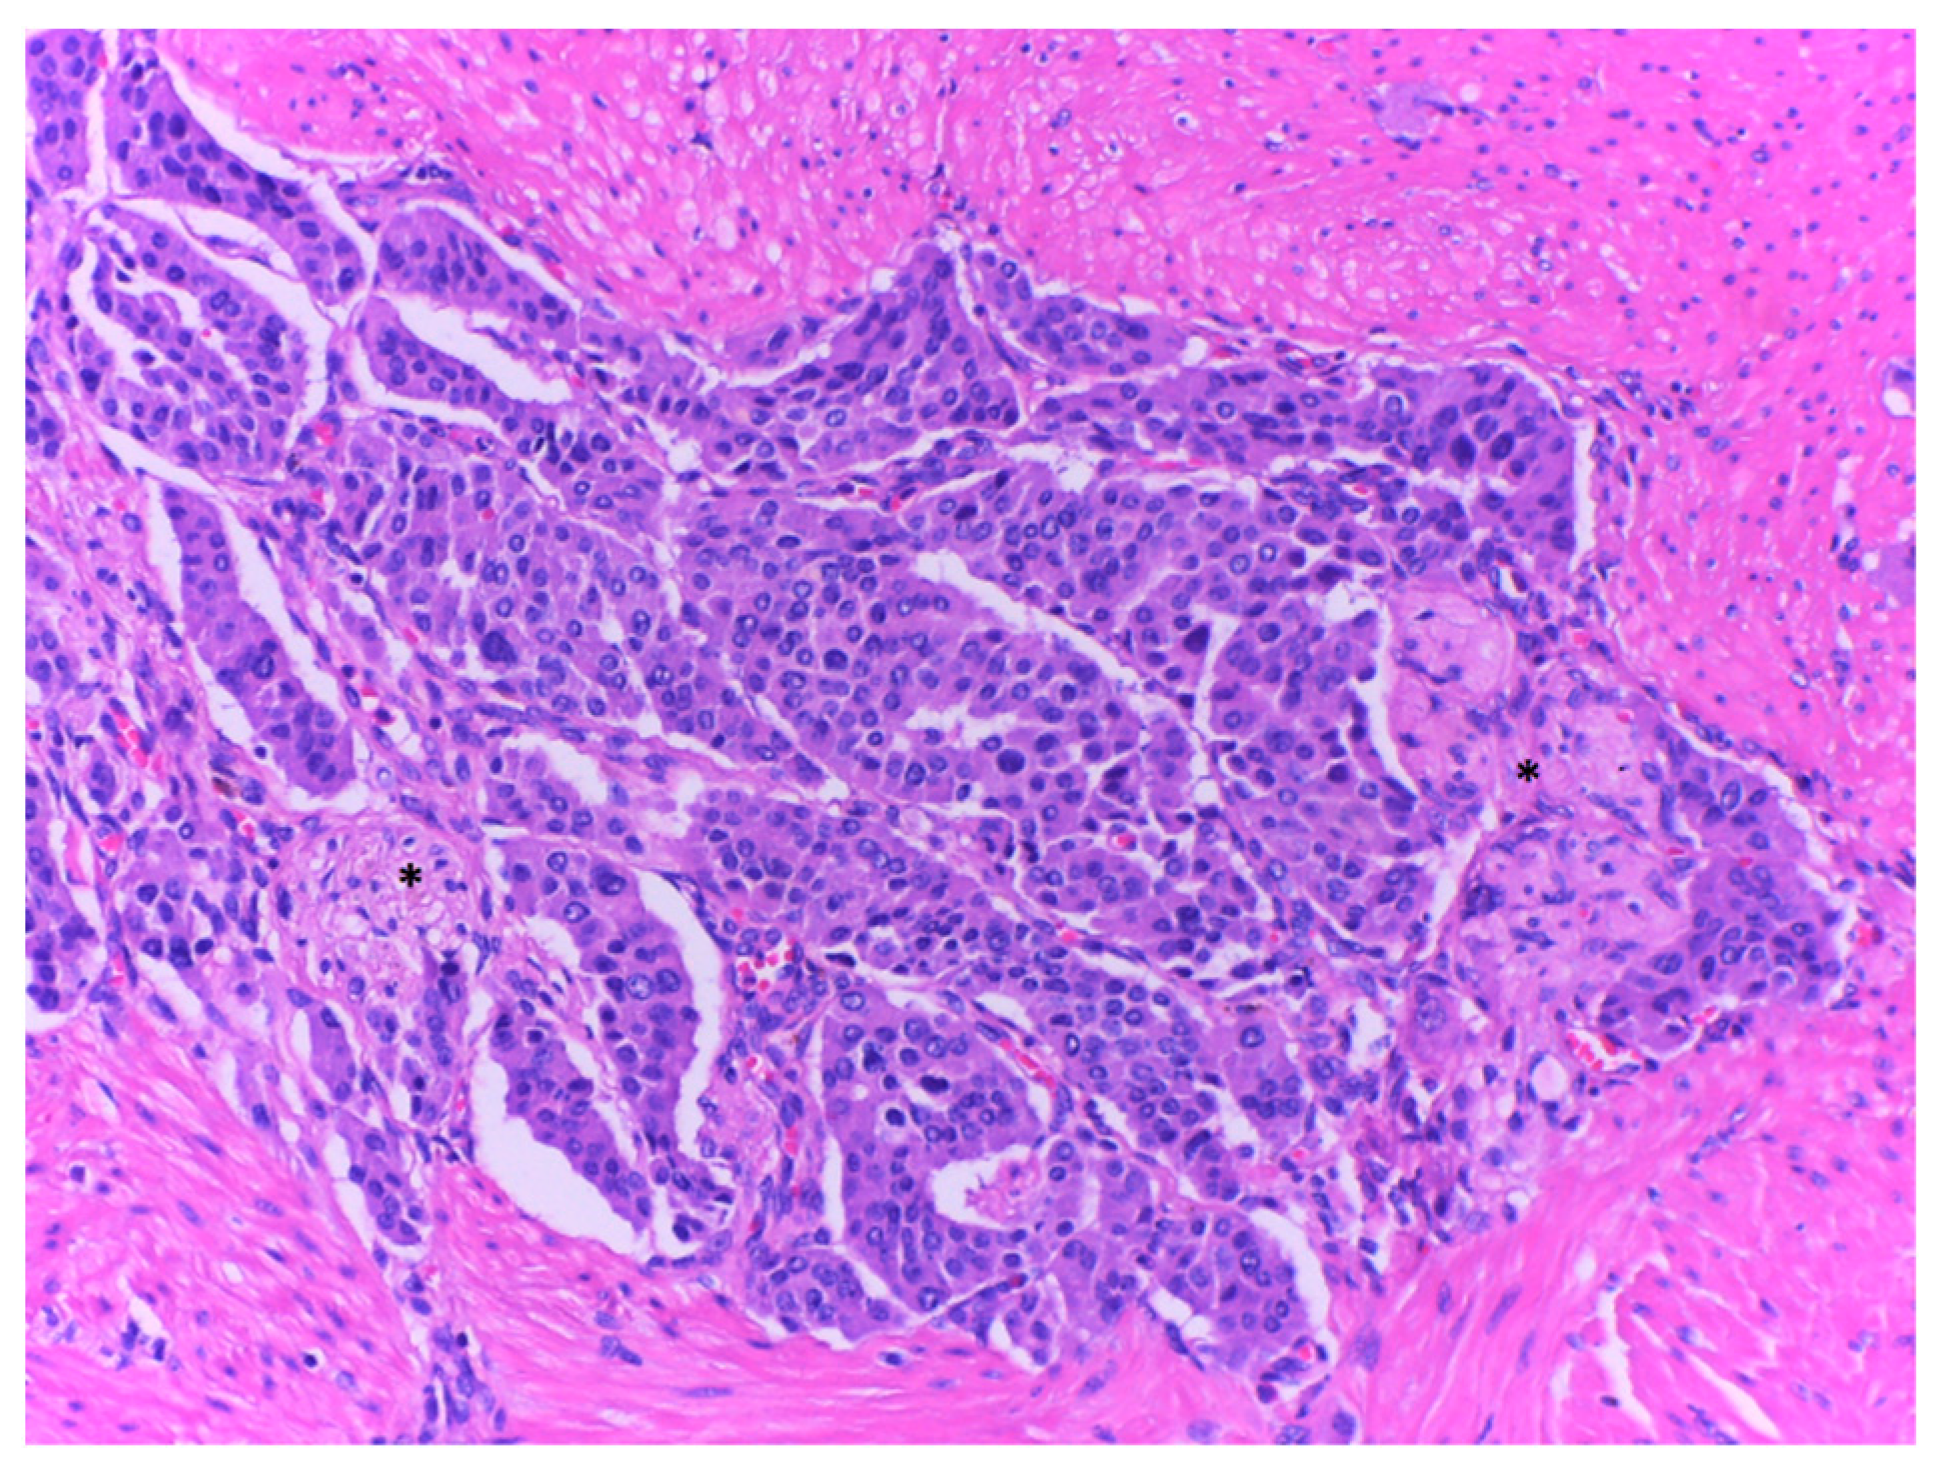

2.4. Histopathological Exam

| Sample | Sample | Sample 1 | Sample 2 | Sample 3 | Sample 4 |

| Aspect | Tumor proliferation with cells containing round, oval, pleomorphic nuclei, and fine granular chromatin. Proliferation covered the entire section and caused partial ulceration of the mucosa that crosses muscular propria layer and extends into the peripancreatic adipose tissue with discrete infiltration of pancreatic acini. Infiltration was clearer after synaptophysin labeling. | Tumor proliferation with atypical cells, fasciculate disposition, elongated nuclei, discrete nucleoli, and pale eosinophilic cytoplasm. The apparent origin of the tumor is muscularis propria | Small intestine sample with tumor proliferation, composed of cells with fascicular disposition, elongated and non- pleomorphic nuclei, pale eosinophilic cytoplasm, rare epithelioid cells. The apparent origin of the tumor is muscularis propria | Sample muscle proliferation with tumor proliferation composed of cells without atypia, fascicular disposition, elongated nuclei, discrete nuclei, and pale eosinophilic cytoplasm | Sample muscle proliferation with tumor proliferation composed of cells without atypia, fascicular disposition, elongated nuclei, discrete nuclei, and pale eosinophilic cytoplasm |

| Tumor cells | CgA-positive SPY-positive Ki67-reduced, maximum 2% | c-kit-positive DOG1 positive SMA-negative | c-kit-positive DOG1 positive SMA-negative CgA-negative | c-kit-positive SMA-negative | c-kit-positive SMA-negative |